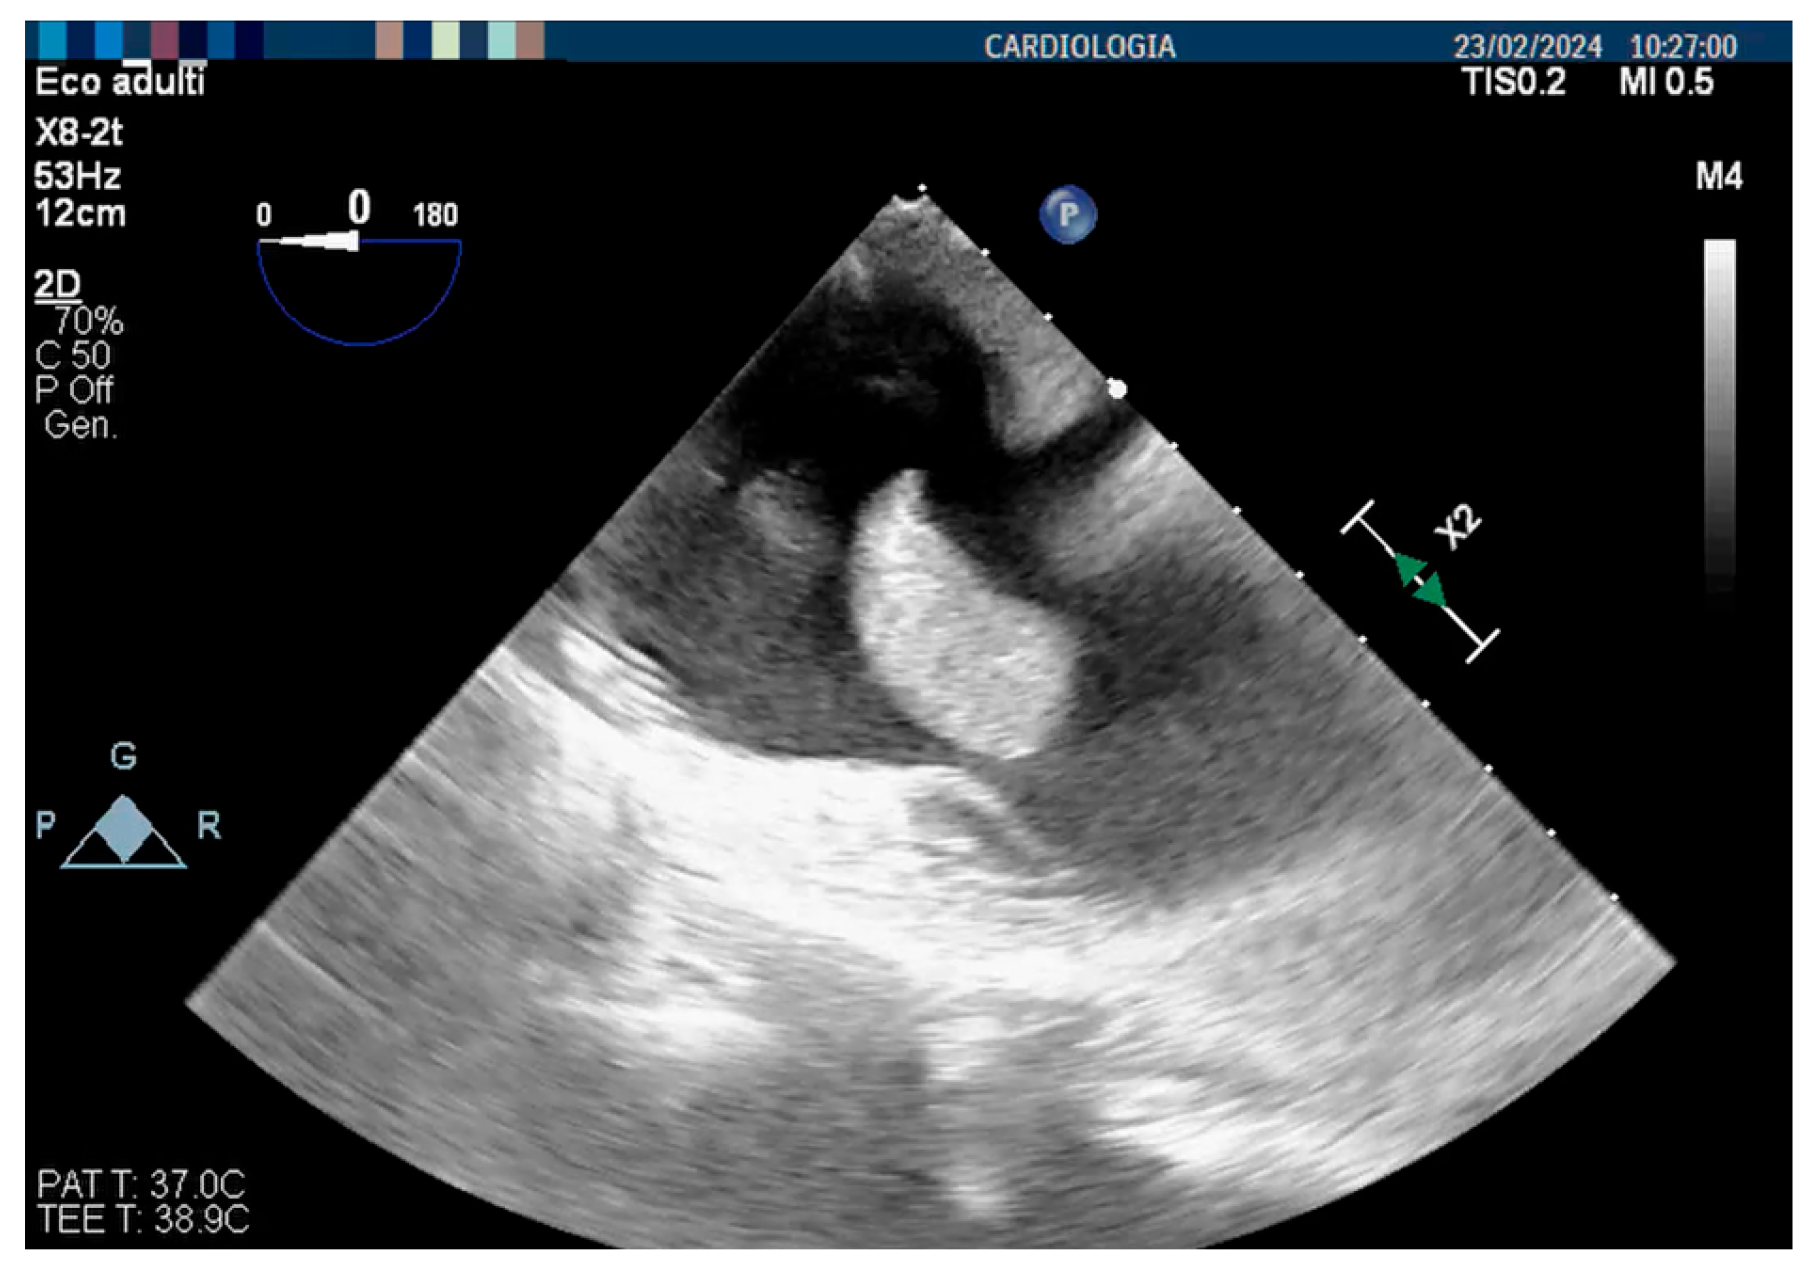

2. Literature Search

3. Case Report